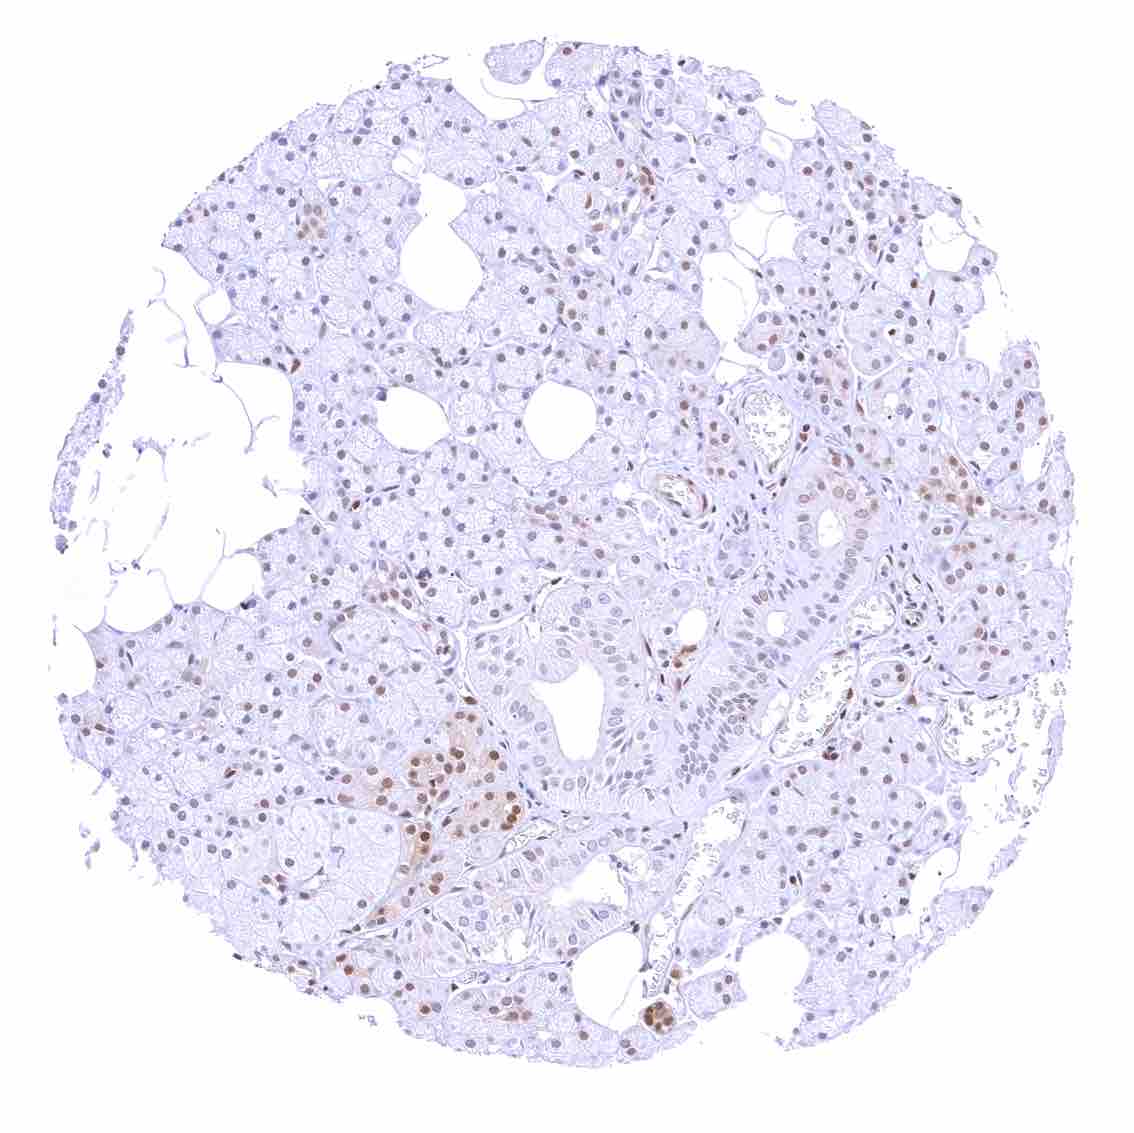

Kidney, cortex – Tubuli are usually p27 negative. The strongest p27 staining occurs in glomeruli and in stroma cells including small vessels.